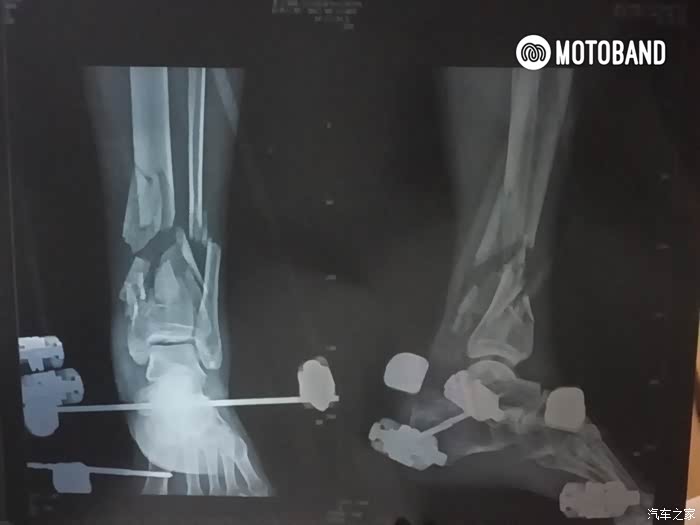

2017.8.8凌晨 朝阳急诊ICU 刚刚做完手术麻醉醒了

伤的有多重呢,医生说:除了连着点皮肉,该碎的该断的都断了,差点脚就没了。

左胫腓骨远端开放粉碎性骨折